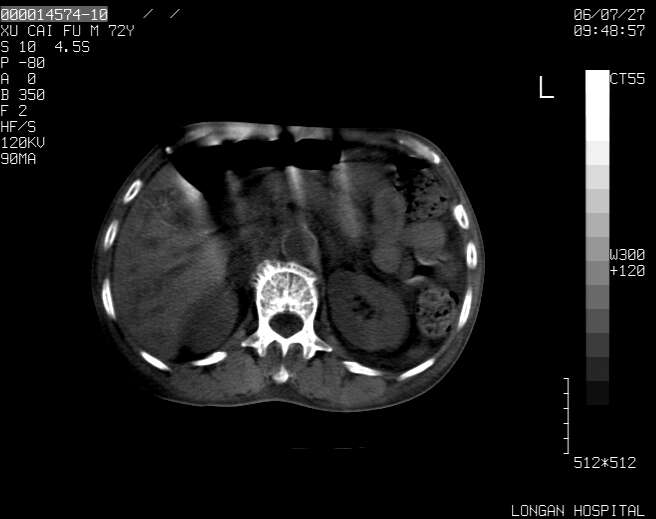

以下是引用winter在2006-7-30 20:14:00的发言:[br]1、考虑胆囊癌伴胆道侵犯并高位胆道梗阻、肝内多发转移、腹膜后淋巴结转移。[br]2、右肾轻度积水。[br]3、老人家72岁了胰腺头体尾部均较饱满,不过未见密度异常及其他异常征象。[br]4、腹水。

以下是引用jiajie在2006-7-31 7:10:00的发言:[br]考虑肝转移瘤,腹膜后淋巴结增大。[br]胃癌不能除外,建议胃镜检查。